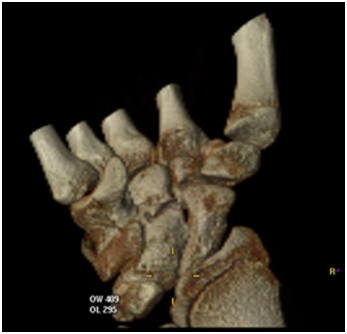

The X-rays showed the presence of a large bone tumour arisen from the lunate bone, not showing the actual involvement of the tumour in the carpal joints (Figure 2A); the subsequent CT scan confirmed the more accurate extension of the mass showing how the osteochondroma expanded dorsally and proximally, reducing and invading the ulno-carpal space (Figure 2B &2C), and also in the lateral view was easy to see how the deformed lunate had an expansion of the volar rim up to the neck of the capitate, reducing the midcarpal motion as well (Figure 2D).

Figure 2B & C 3D CT scan of the Lunate osteochondroma

Figure 2D Lateral view showing the extension of the volar rim of the Lunate  up to the neck of the Capitate.